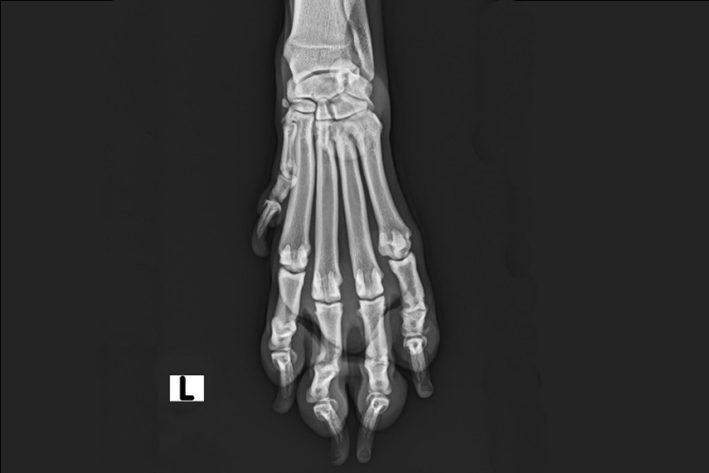

Röntgenbild Primäre Zehengelenksarthrose

Primäre Zehengelenksarthrose